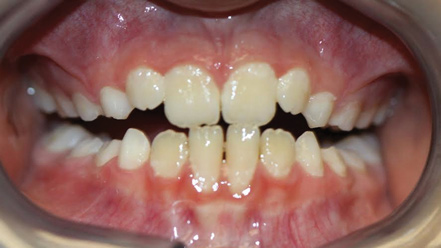

Fig 6. Patient with cleft palate treatment history and underdeveloped craniofacial growth, facial view (Fig 6) and occlusal view (Fig 7).

Figure 6

Fig 7. Patient with cleft palate treatment history and underdeveloped craniofacial growth, facial view (Fig 6) and occlusal view (Fig 7).

Figure 7

Although the face is a 3-dimensional structure, craniofacial growth modification is a topic that may be stratified by reviewing the transverse, vertical, and anterior-posterior dimensions. A transverse growth inadequacy is often illustrated in the form of a posterior (and often anterior) crossbite.21 The most common cause of this inadequacy is an underdeveloped maxilla, or, alternatively, an overdeveloped mandible; oftentimes a combination of these characteristics is the source of the problem. One example is a patient who has had cleft lip/palate repair, which may lead to craniofacial growth restriction in all dimensions (Figure 6 and Figure 7). When considering the transverse dimension, the most common treatment for a posterior crossbite is RPE therapy.21 In mild cases, archwire or dental expansion may suffice.